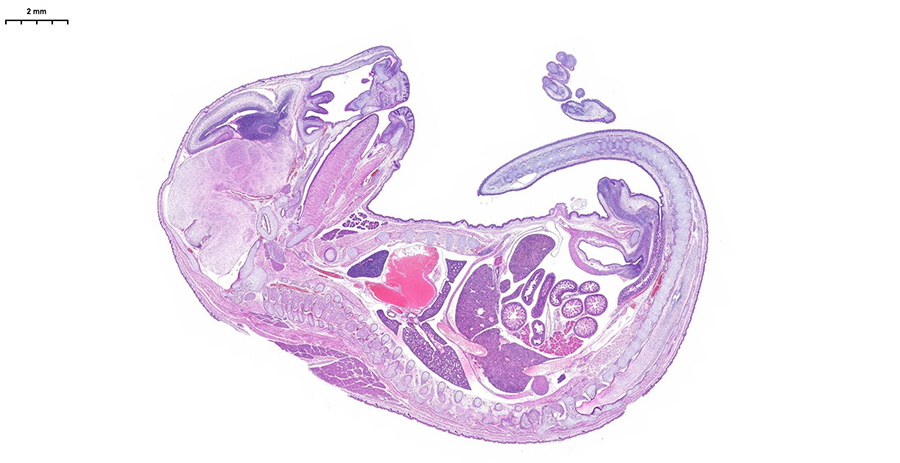

Погрузитесь в будущее гистологической лаборатории на двухдневном мероприятии, где представится возможность поработать с новейшим гистосканером LG-S80 от Servicebio.Погрузитесь в будущее гистологической лаборатории на двухдневном мероприятии, где представится возможность поработать с новейшим гистосканером LG-S80 от Servicebio.

Сможете оценить высочайшее разрешение, скорость обработки (полное стекло за 3-5 минут) и интеллектуальное аналитическое ПО, которое автоматически распознаёт структуры и формирует количественные отчёты с готовыми данными. Можно принести для апробации свои образцы, демонстрируемая конфигурация флуоресцентных каналов (Ex/Em, нм):